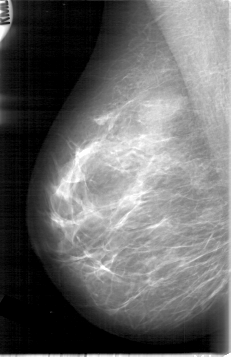

D_4006_1.LEFT_MLO

LEFT_MLO LINES 5281 PIXELS_PER_LINE 3571 BITS_PER_PIXEL 12 RESOLUTION 43.5 OVERLAY